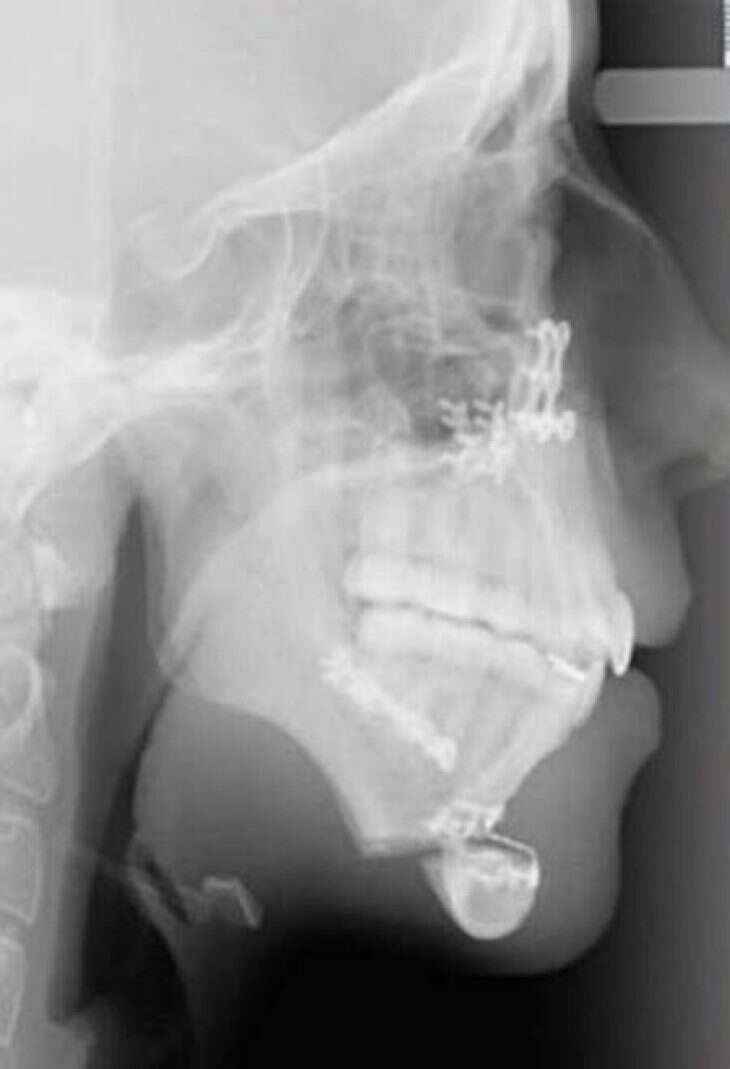

Η ίδια και ο οικογενειακός της περίγυρος αποφάσισαν να μη μείνουν με σταυρωμένα χέρια. Θέλησαν να προχωρήσουν σε μία χειρουργική επέμβαση. Μέσω αυτής της επέμβασης επιδιώκονταν να διορθωθούν όσα ενοχλούσαν την Ellie Jones, τα οποία κρατούσαν και την ψυχολογία της στο ναδίρ.

Η οικογένεια επισκέφθηκε έναν γναθοχειρουργό, ο οποίος βοήθησε στη μεταμόρφωση της Ellie Jones. Το πρώτη χειρουργείο προκάλεσε πολύ πόνο στην 20χρονη. Ήταν ιδιαίτερα δύσκολο σαν χειρουργείο και στο τέλος του έπρεπε να κάνει σωστή διατροφή. Αυτή εμπεριείχε μόνο υγρά για χρονικό διάστημα ενός μηνός, ενώ στο ξεκίνημα δεν μπορούσε να μιλήσει.

Στο χειρουργείο, που ακολούθησε, το οποίο ήταν δεύτερο κατά σειρά μπόρεσε να διορθώσει το πηγούνι της. Έτσι, μπόρεσε να μεταμορφωθεί και να φτιάξει παράλληλα και την ψυχολογία της.